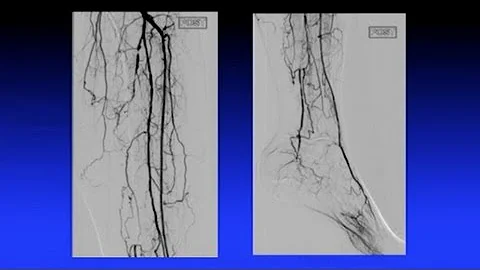

Pantharis And Image-guided Atherectomy - Ian Cawich, Md

Presentation recorded at Cardiovascular Innovations 2017. CVI2017 was hosted by Cardiovascular Innovations Foundation at the ...